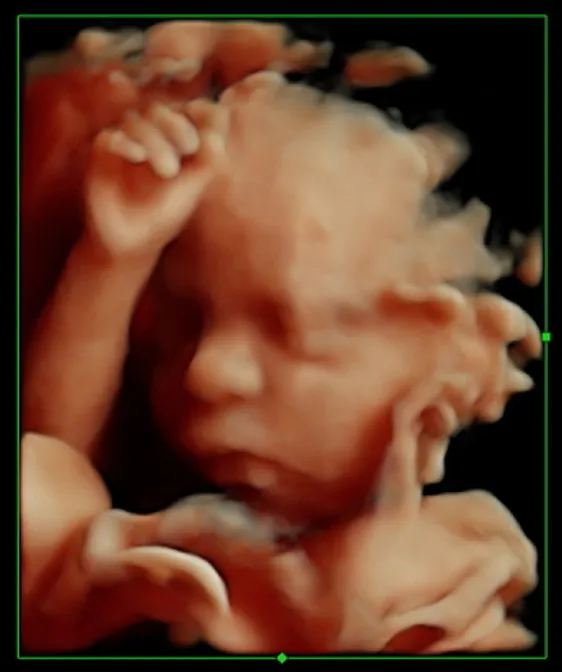

Ultrasonido 3D,4D Y HD Live

Durante todo el embarazo se puede realizar Ultrasonido 3D, 4D y HD-Live, también se conoce como “caritas de bebé”, este se realiza siempre y cuando la posición del bebé lo permita y después de haber evaluado su salud con el ultrasonido 2D, se obtienen imágenes de la carita, sólo logra ver la parte externa de bebé, no visualiza las estructuras internas como corazón, cerebro, etc.